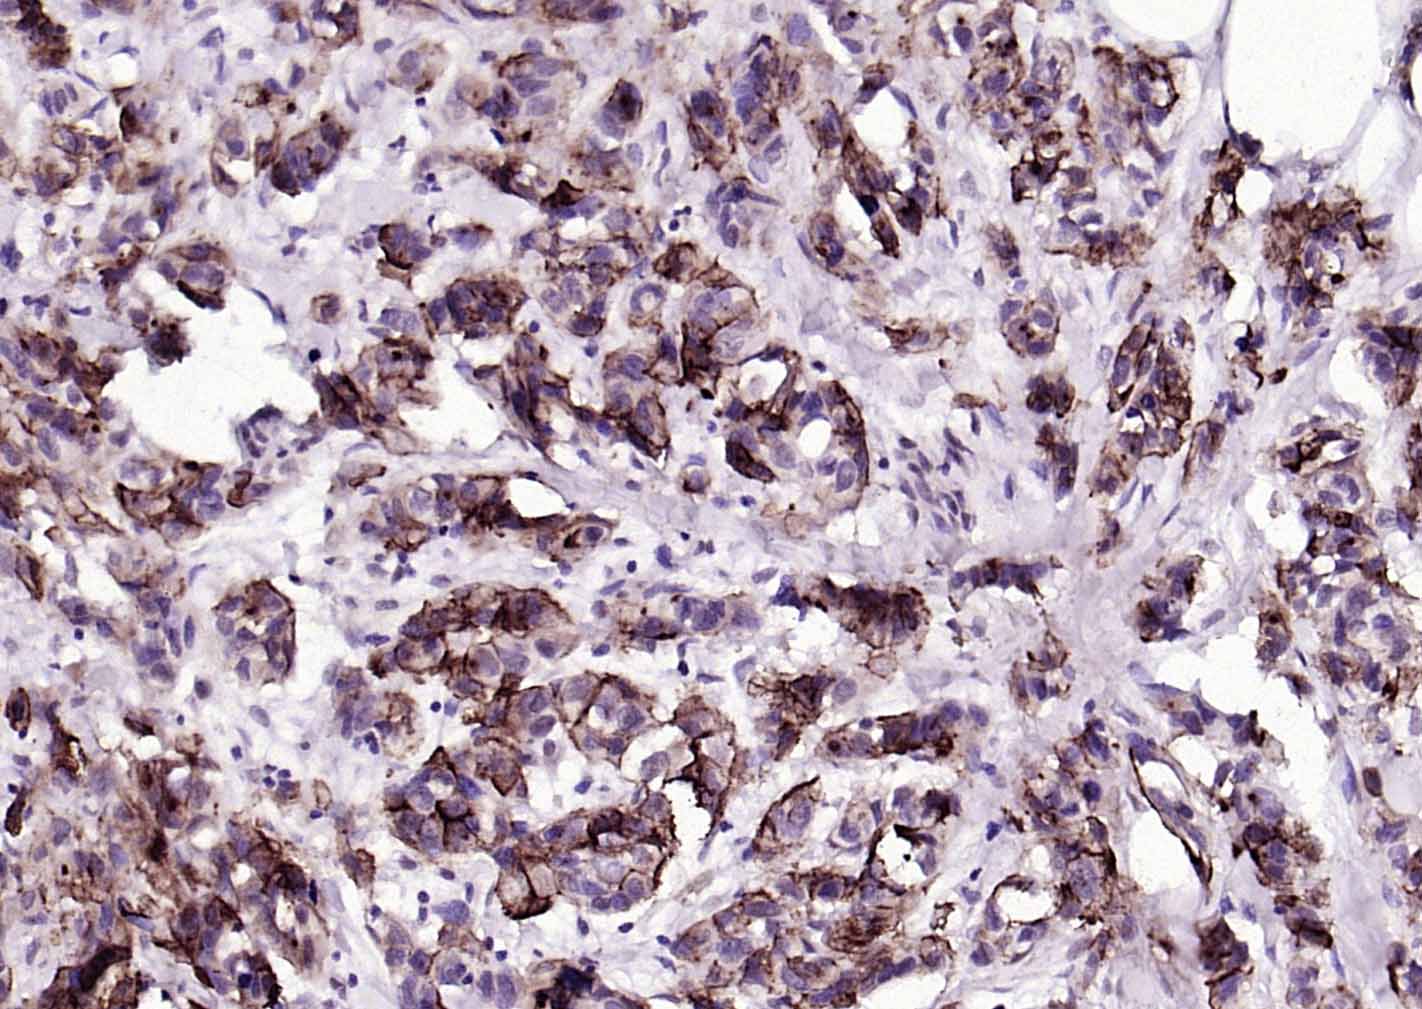

IHC-PHuman1:100-500

交叉反应: Human